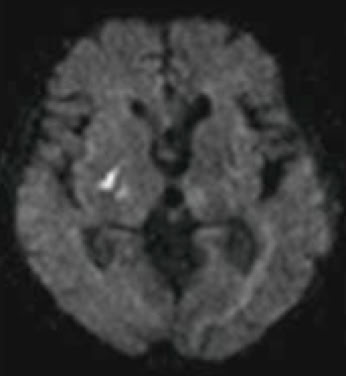

2. 脳MRI:MRI(0.4TオープンMRI)による脳の断層撮影です.

脳腫瘍(脳のできもの),脳梗塞,脳萎縮などを判定します.

脳梗塞のMRI画像

MRI(脳梗塞急性期)